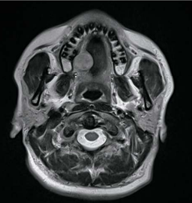

症例1

75歳男性。

疼痛などの自覚症状が無かったため、受診せずに放置。

そのため、ここまで大きくなってからの受診となりました。

参考画像